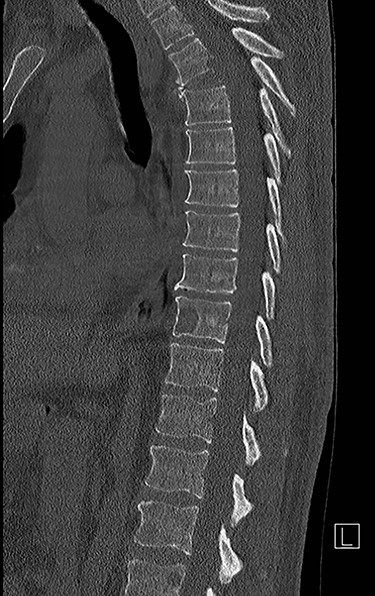

Sagittal computed tomography (CT) scan demonstrated multiple lytic lesions and pathological fracture of the T4 vertebra with almost complete collapse along with kyphotic deformity.